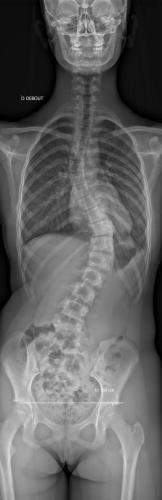

Images de scolioses opérées 16 janvier 202418 janvier 2023 par Damien Scoliose thoraco-lombaire 1 Radio préopératoire de Face Radio préopératoire de Profil Radio de Face à 2 ans de recul Radio de Profil à 2 ans de recul